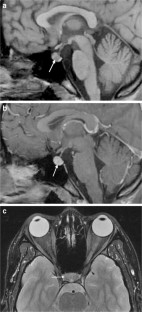

Fig. 2